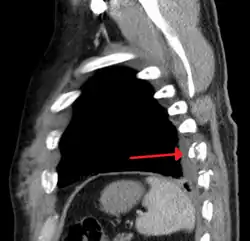

| An X ray showing multiple old fractured ribs of the person's left side as marked by the oval | |

Illustration showing rib fracture at 3rd, 4th and 5th rib -

Right sided pneumothorax and rib fractures -

Two broken ribs as seen on parasagittal CT